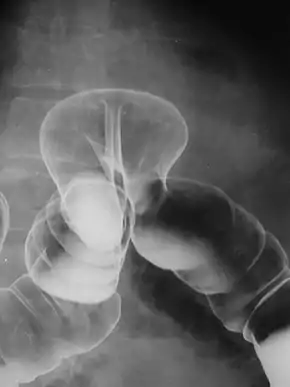

A lower gastrointestinal series is a medical procedure used to examine and diagnose problems with the human colon of the large intestine. Radiographs (X-ray pictures) are taken while barium sulfate, a radiocontrast agent, fills the colon via an enema through the rectum.

![]() Radiograph of a barium enema displaying a colonic herniation. | |